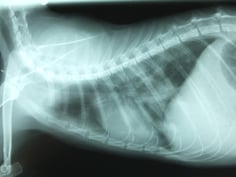

【レントゲン検査】

臓器や構造物の位置、大きさ、形などの変化を調べます。